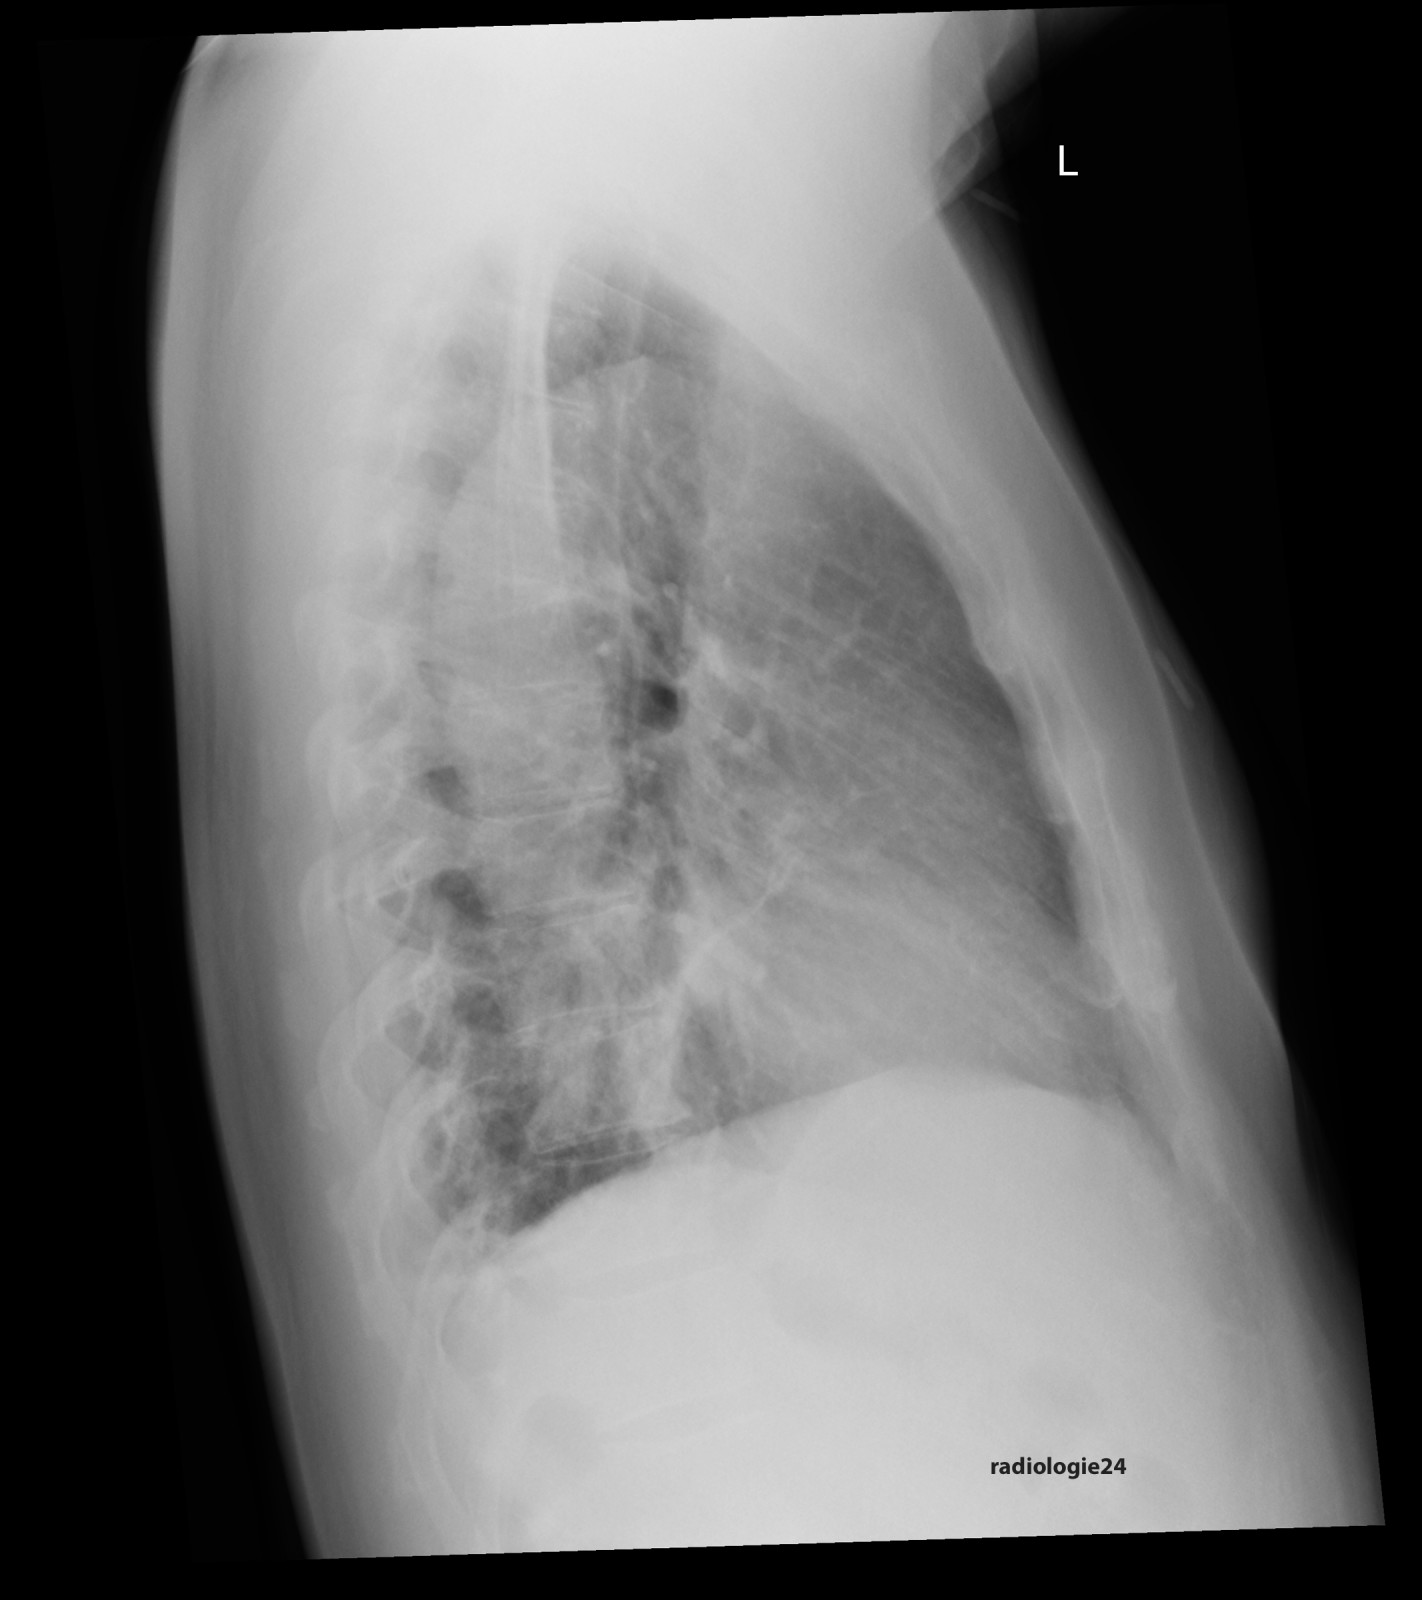

Röntgenfall des Monats Oktober 2017 mit Auflösung

48 jähriger Patient. Klinische Angaben: Thoraxschmerzen, afebril, hypertensiv entgleist. Fragestellung: Infektzeichen? Kardiale Kompensation? Diagnose? Weitere radiologische Diagnostik?

Bild vergrössern

Link zur Auflösung mit ausführlichem Befund

https://www.radiologie24.ch/radiologie-mediathek/roentgenfall_des_monats